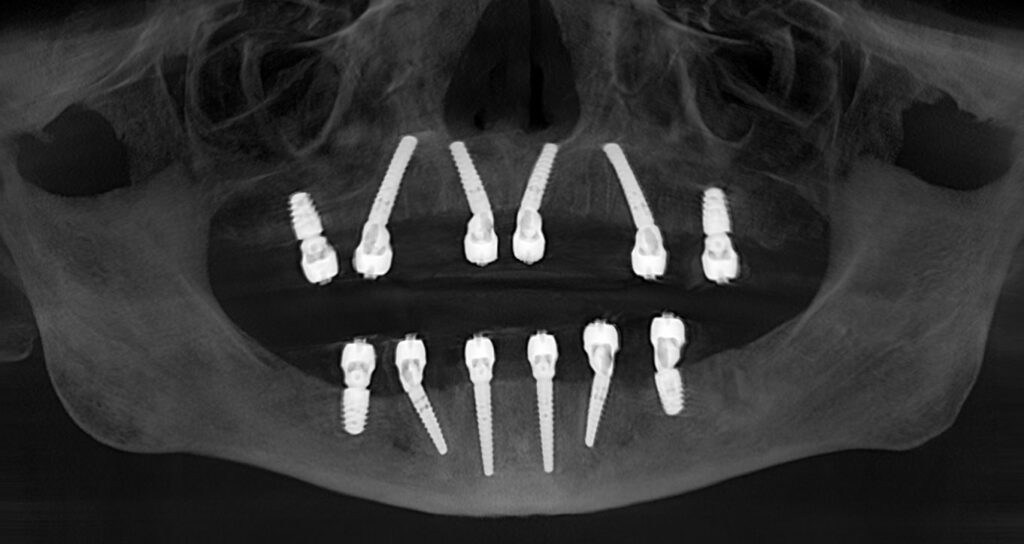

Treatment Planning

Our team digitally maps the new smile, determining implant number, positioning, and prosthetic design for long-term stability and esthetics.

Implant Placement

Using precise, guided surgical protocols, implants are placed to create a strong, stable foundation for the full-arch restoration.